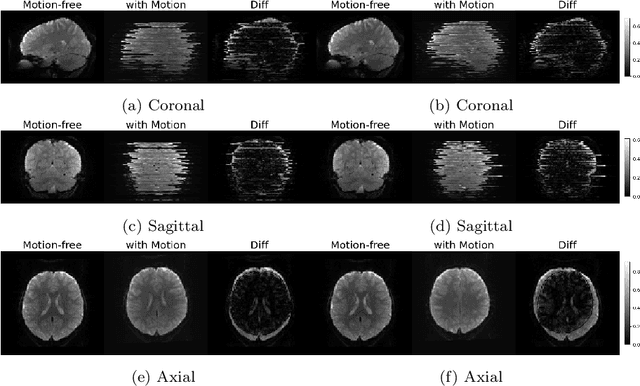

Abstract:Functional Magnetic Resonance Imaging (fMRI) is vital in neuroscience, enabling investigations into brain disorders, treatment monitoring, and brain function mapping. However, head motion during fMRI scans, occurring between shots of slice acquisition, can result in distortion, biased analyses, and increased costs due to the need for scan repetitions. Therefore, retrospective slice-level motion correction through slice-to-volume registration (SVR) is crucial. Previous studies have utilized deep learning (DL) based models to address the SVR task; however, they overlooked the uncertainty stemming from the input stack of slices and did not assign weighting or scoring to each slice. In this work, we introduce an end-to-end SVR model for aligning 2D fMRI slices with a 3D reference volume, incorporating a self-attention mechanism to enhance robustness against input data variations and uncertainties. It utilizes independent slice and volume encoders and a self-attention module to assign pixel-wise scores for each slice. We conducted evaluation experiments on 200 images involving synthetic rigid motion generated from 27 subjects belonging to the test set, from the publicly available Healthy Brain Network (HBN) dataset. Our experimental results demonstrate that our model achieves competitive performance in terms of alignment accuracy compared to state-of-the-art deep learning-based methods (Euclidean distance of $0.93$ [mm] vs. $1.86$ [mm]). Furthermore, our approach exhibits significantly faster registration speed compared to conventional iterative methods ($0.096$ sec. vs. $1.17$ sec.). Our end-to-end SVR model facilitates real-time head motion tracking during fMRI acquisition, ensuring reliability and robustness against uncertainties in inputs. source code, which includes the training and evaluations, will be available soon.